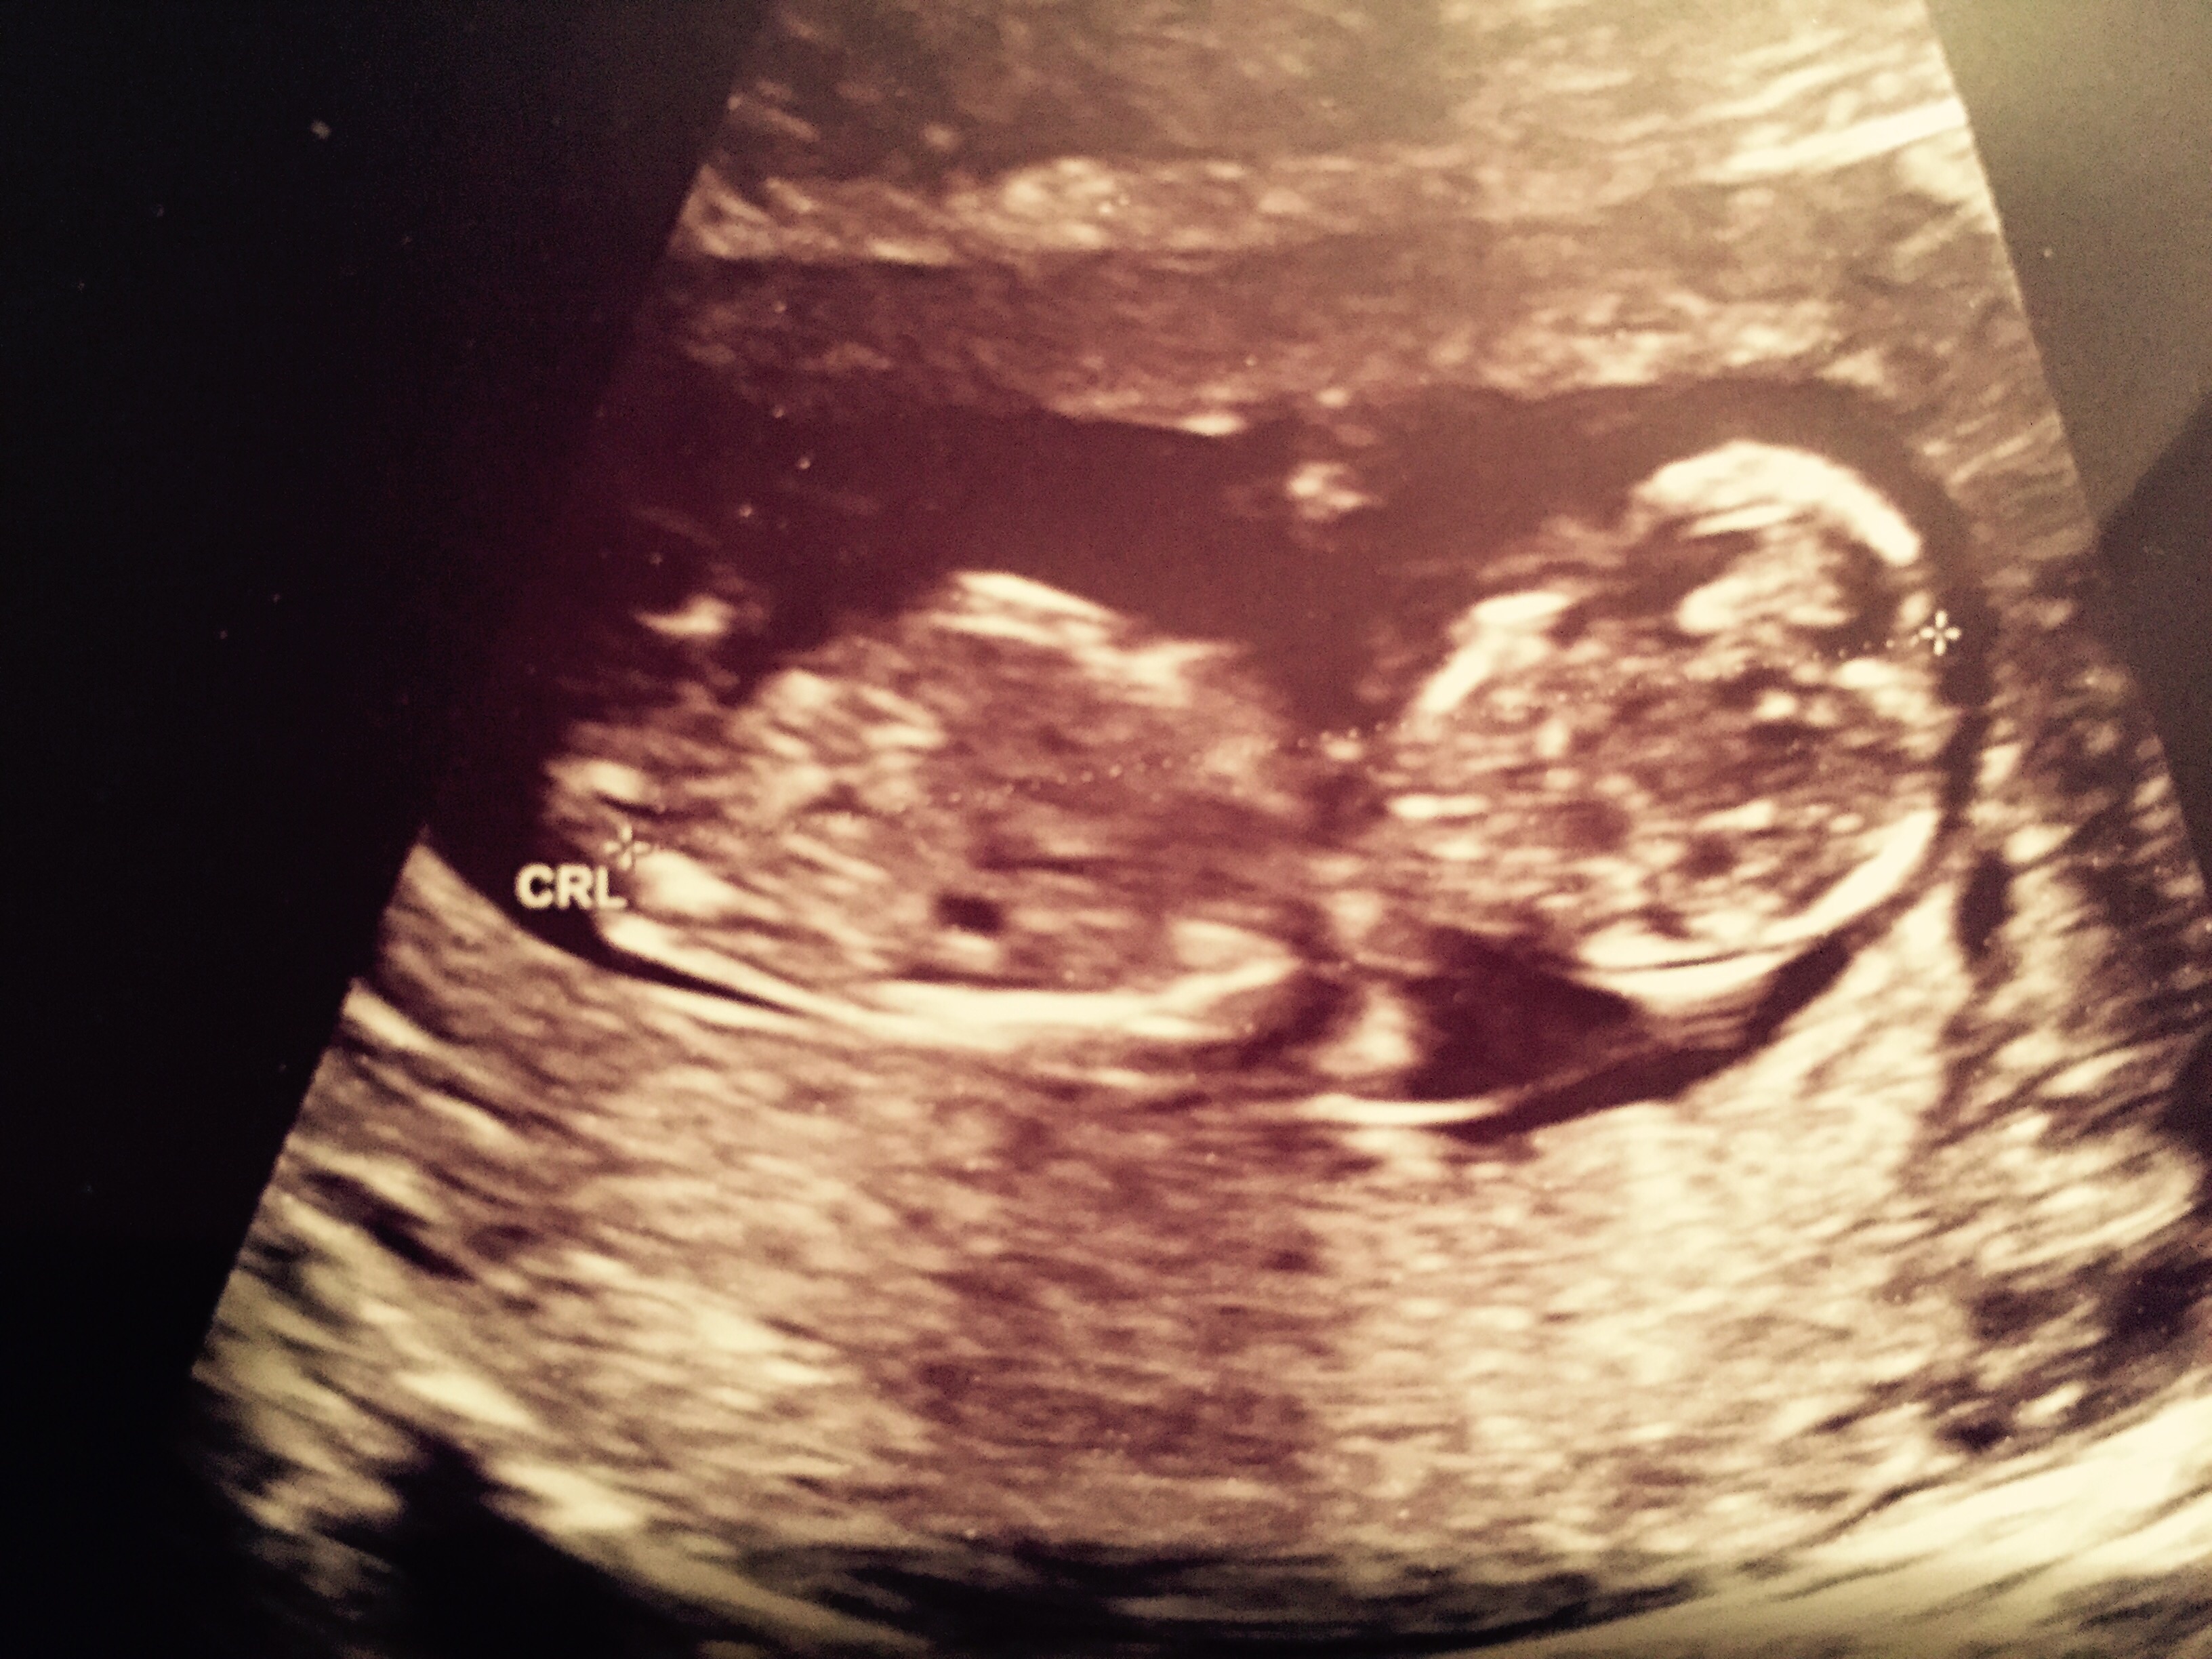

Any guesses using nub theory on this one? Thank u!!!Attachment 30694

Baby is rolling away I don't see any gender clues.